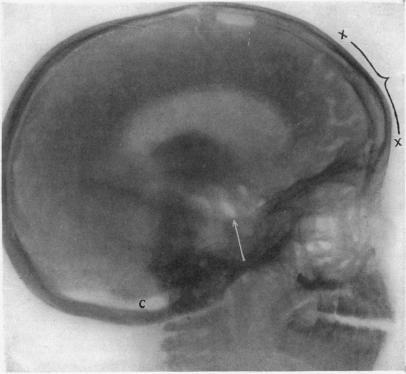

RONTGENOGRAPHY OF THE BRAIN AFTER THE INJECTION OF AIR INTO THE SPINAL CANAL.

Ann Surg. 1919 Oct;70(4):397-403. doi: 10.1097/00000658-191910000-00004.